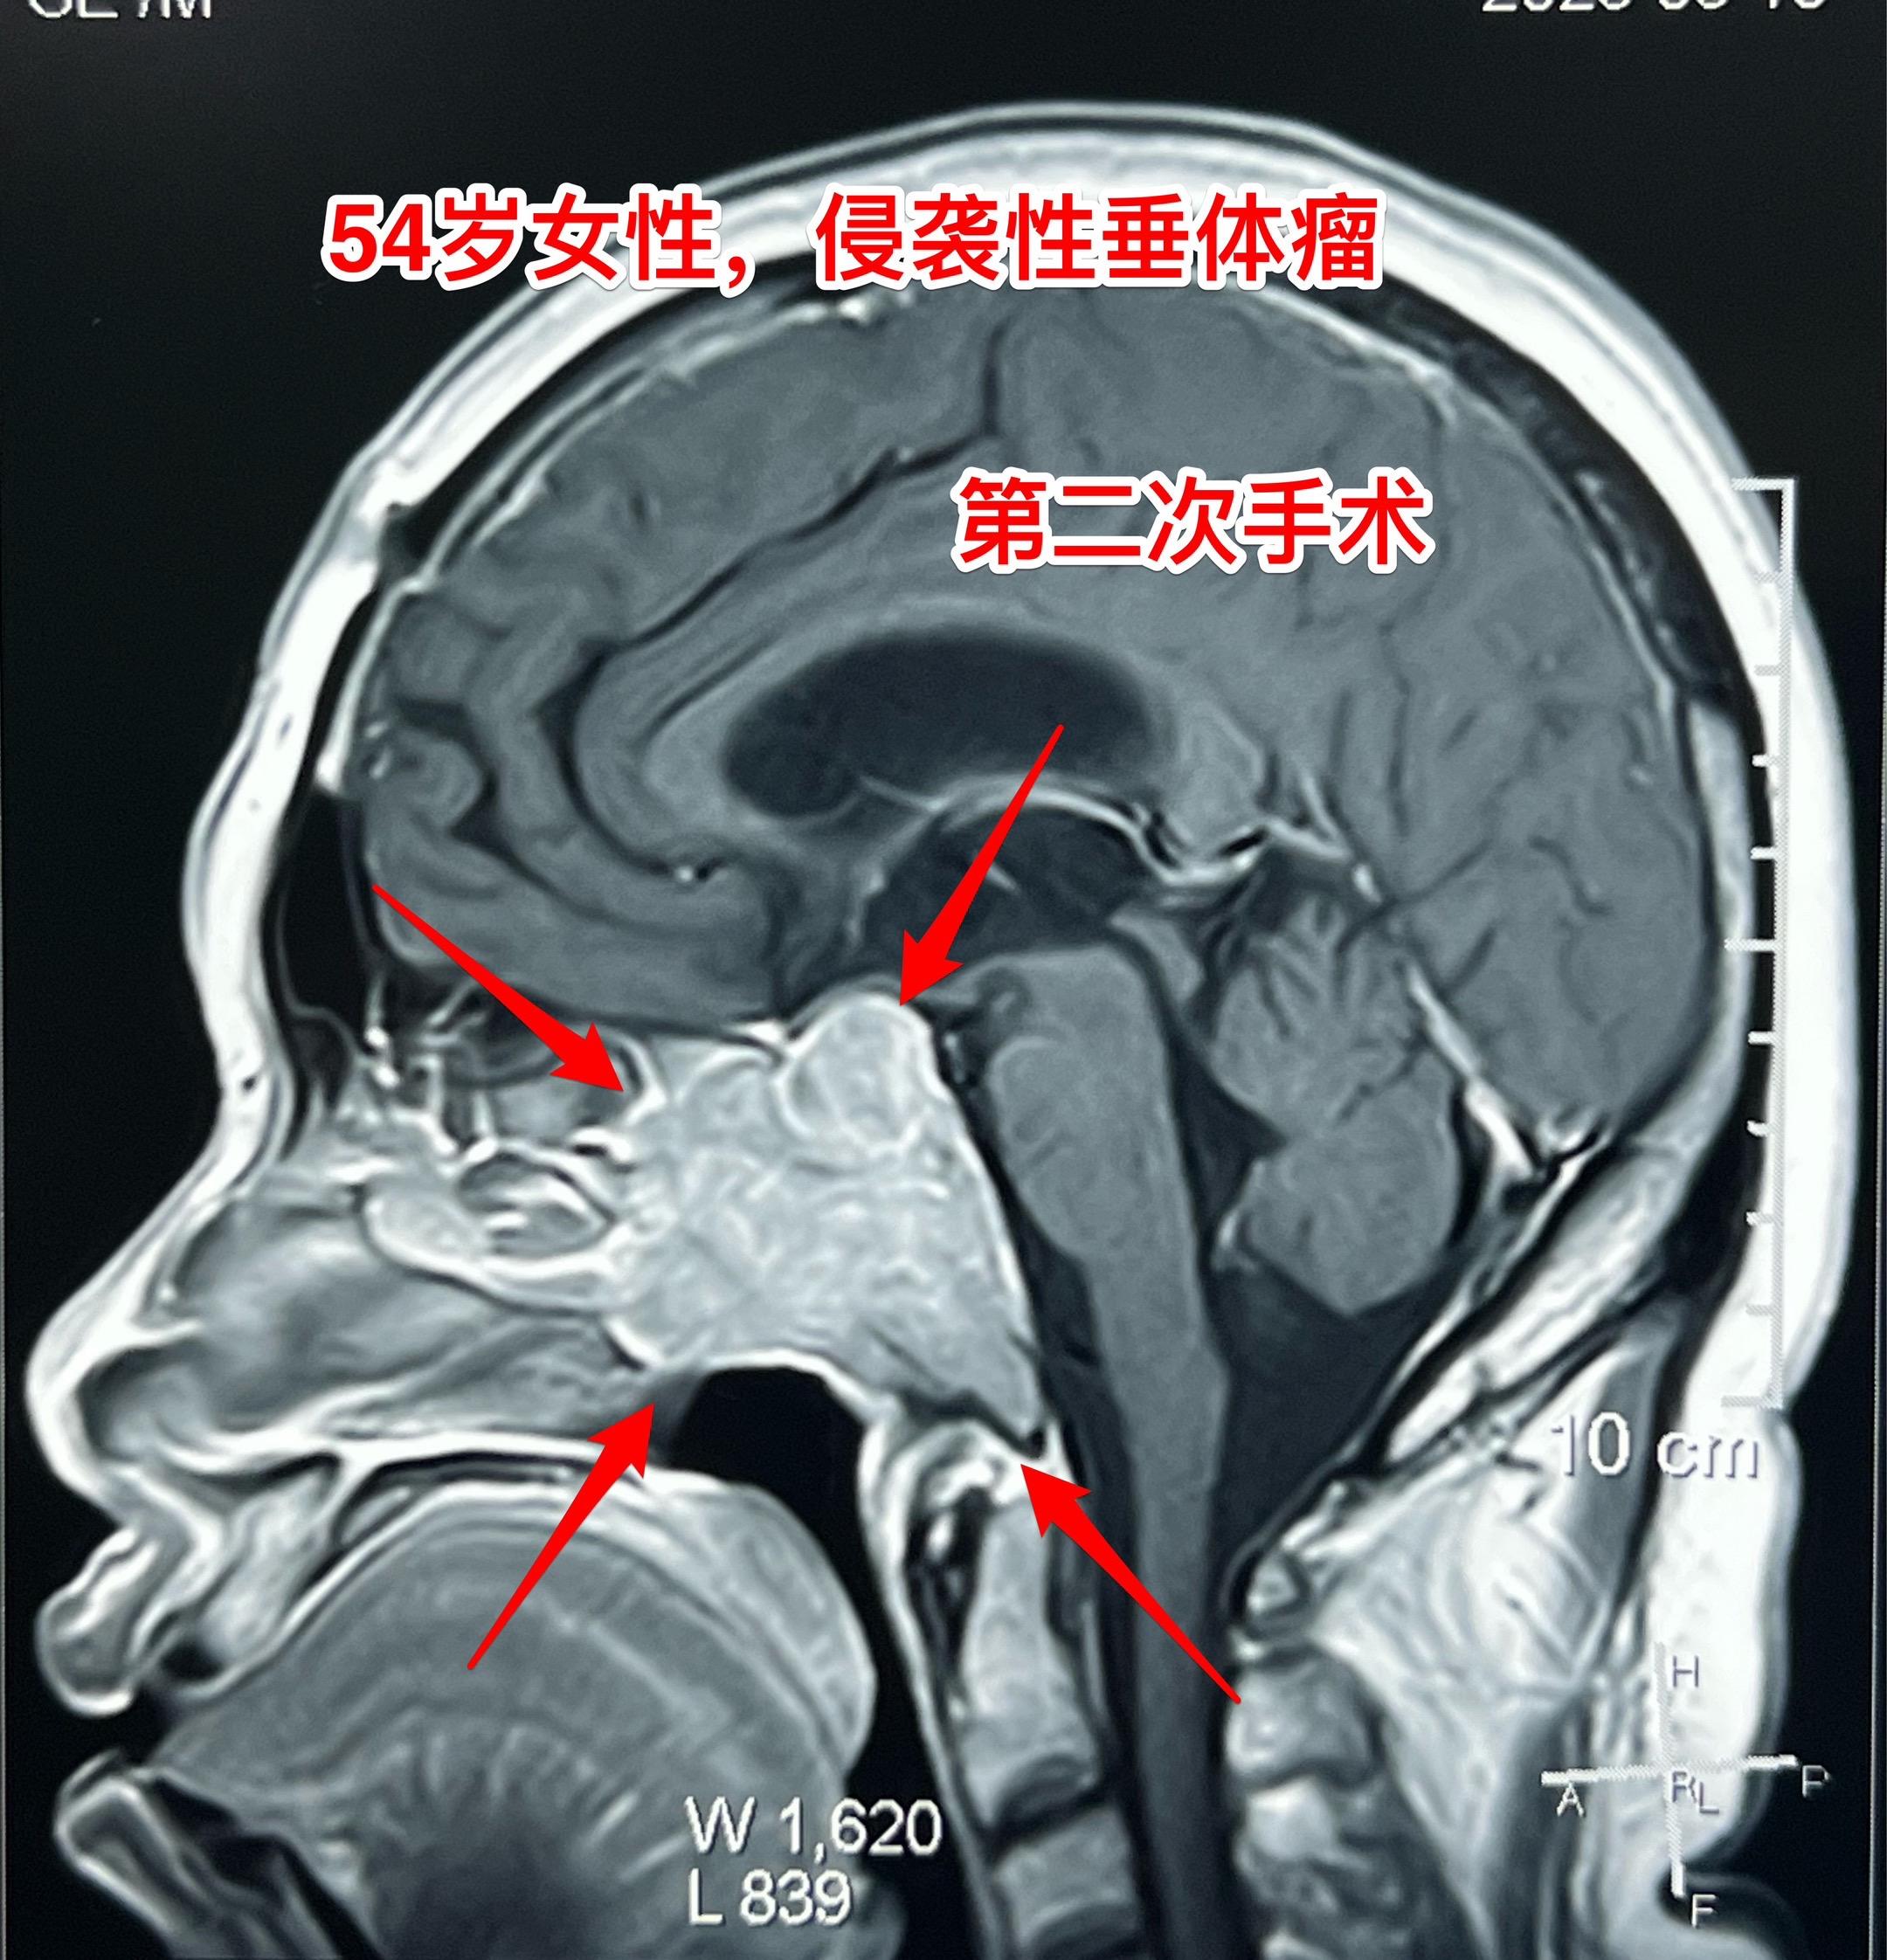

侵袭性垂体瘤第二次手术。54岁女性,2023年9月因垂体瘤作了第一次手术,是开颅手术,当时左眼视力下降。把颅内的肿瘤切除了,蝶窦内、海绵窦内的肿瘤没有动,计划二期手术。 2025年5月病人感觉左眼视力又有下降,来作第二次手术,磁共振、CT显示肿瘤巨大,是典型的侵袭性垂体瘤。这次只能采用经鼻手术了。昨天顺利完成手术。 今天病人没有出现脑脊液鼻漏症状,自感很轻松,精神好。